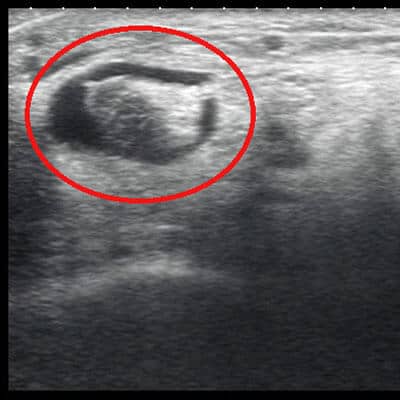

Retrocalcaneal Bursitis

Ankle Sprain

Ultrasound is beneficial in diagnosis of soft tissue injuries including Plantar Fasciitis, Achilles Tendinopathy, Forefoot pathology, Ankle sprain